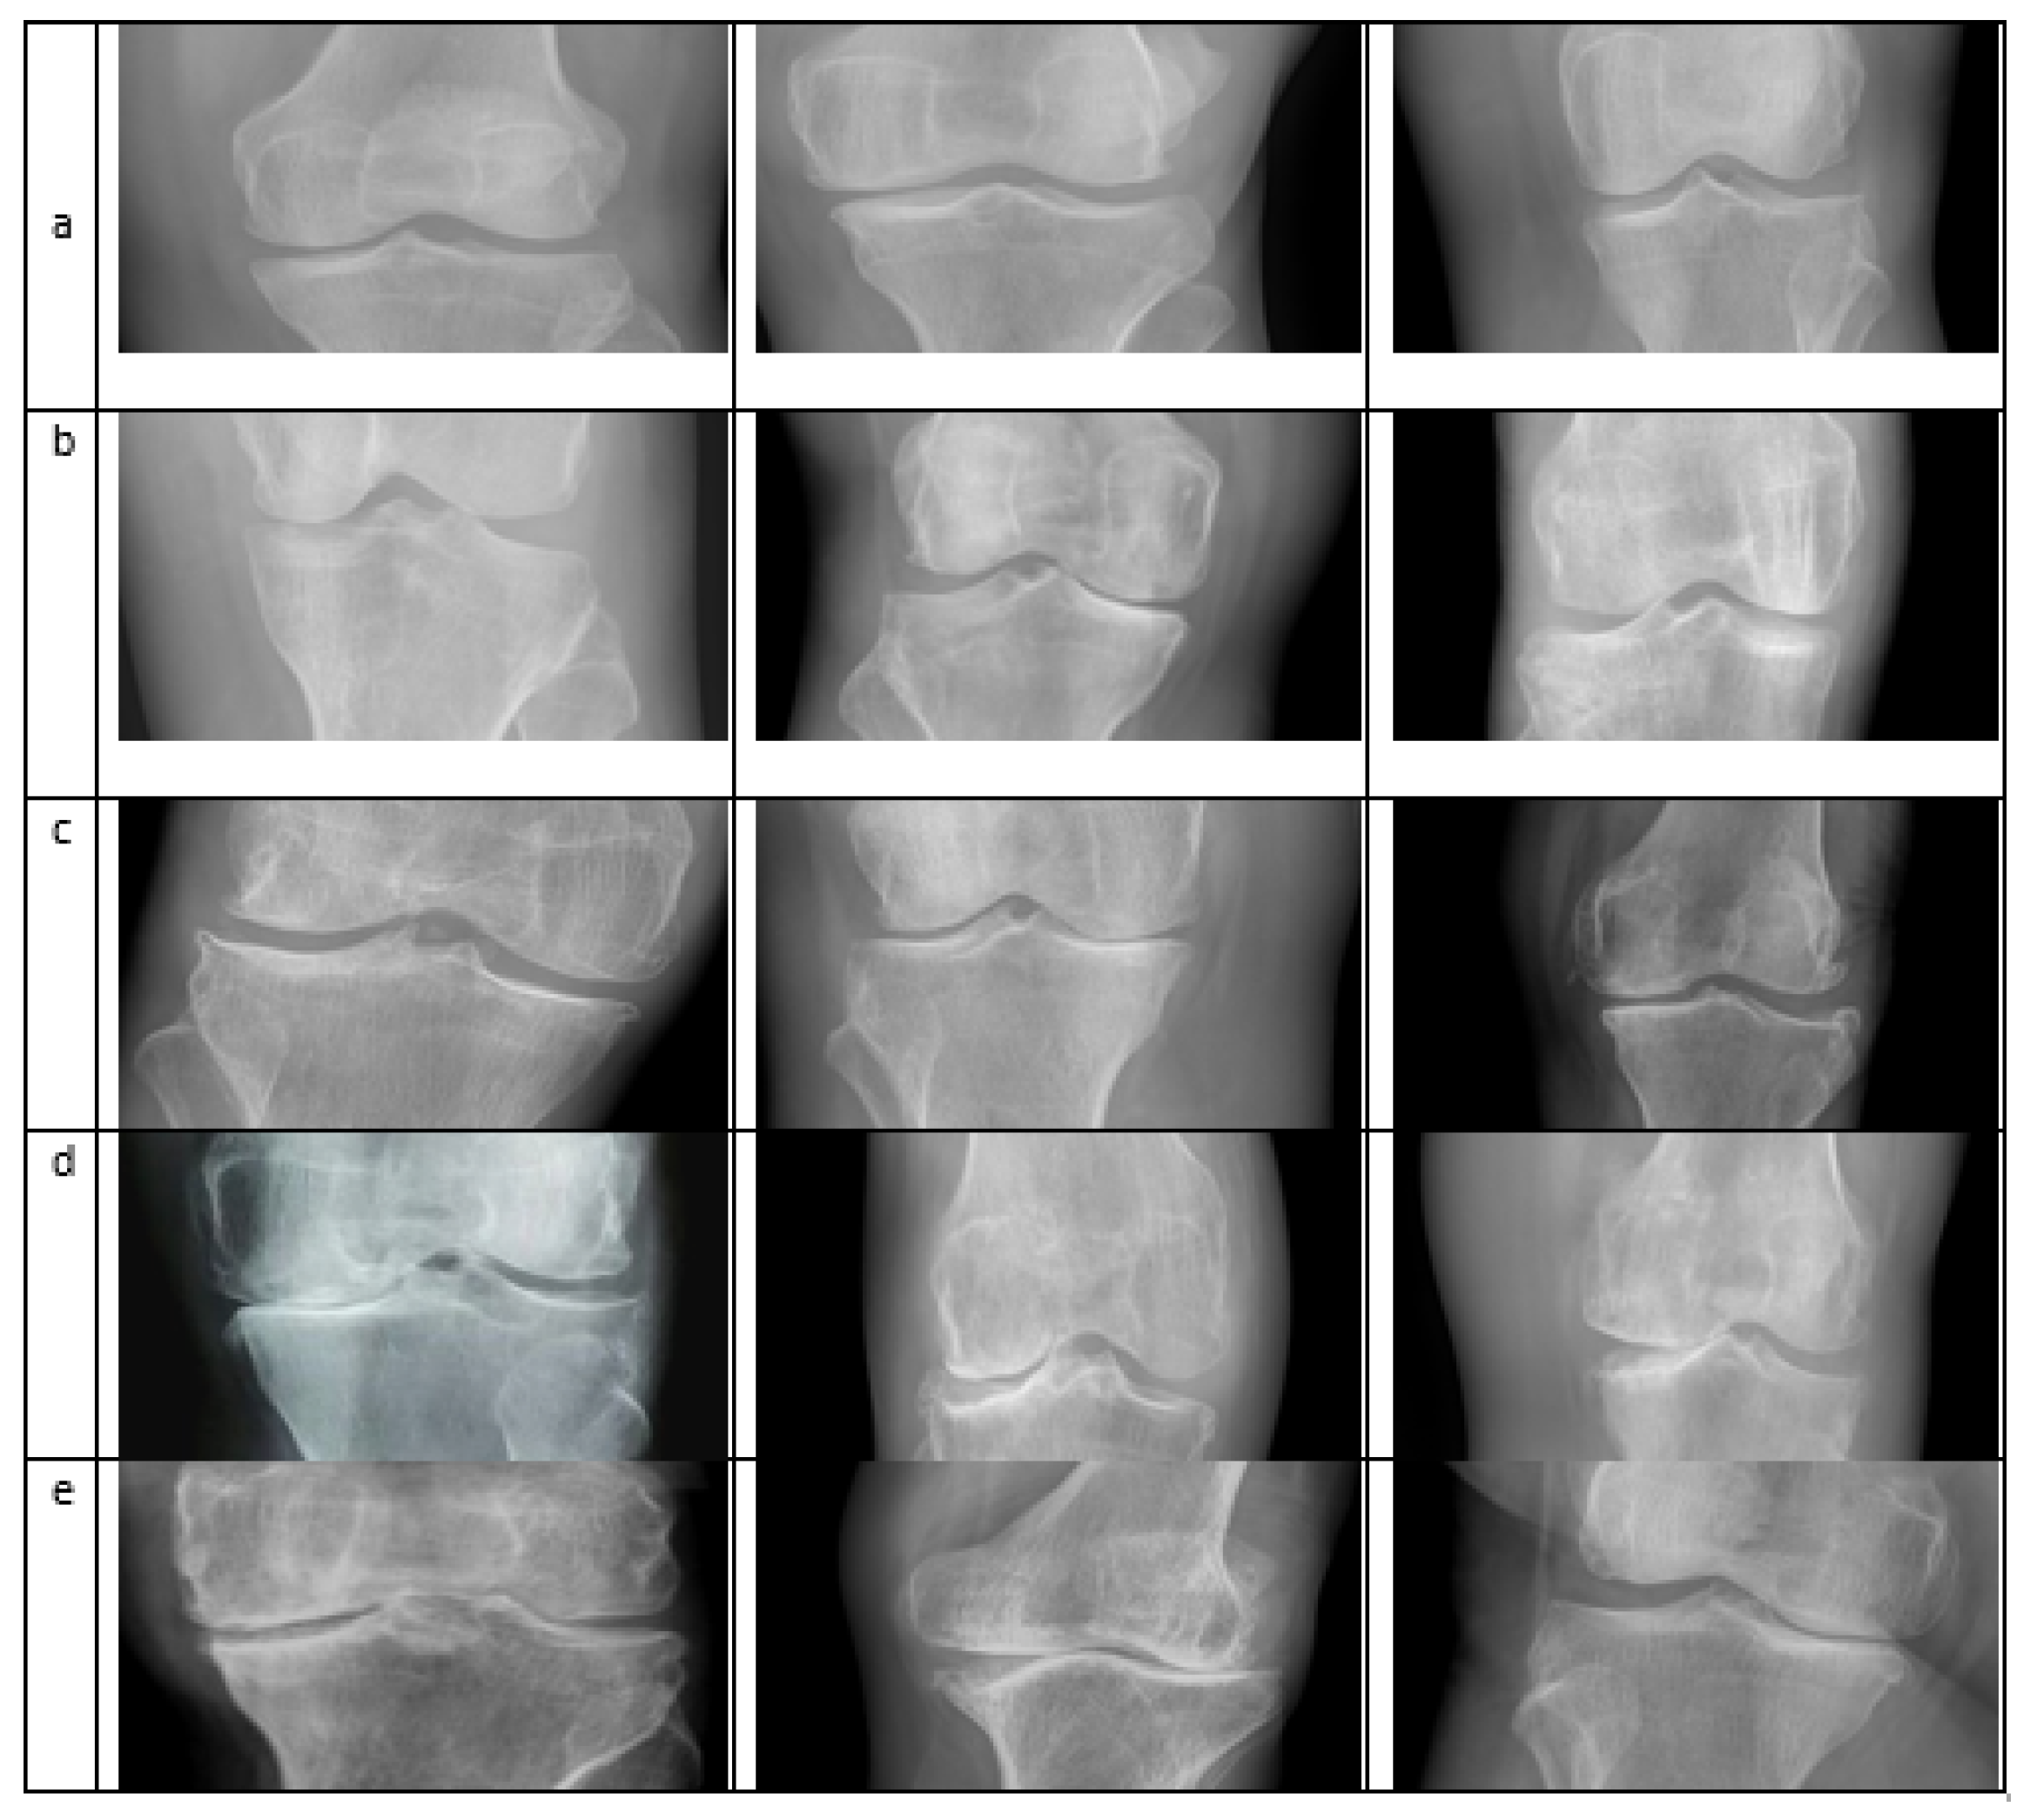

4.1. Dataset